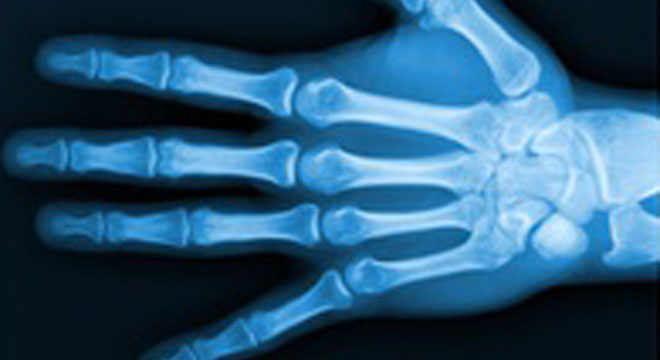

Handgelenksbruch: Röntgenbild Handgelenk

Meist ahnt der Arzt schon bei der Untersuchung und Überprüfung des Handgelenkes, dass es sich um eine Radiusfraktur handelt. Sicherheit gibt das Röntgenbild.

Dabei unterteilt der Arzt die Frakturen in drei Kategorien:

• Typ A: Extraartikulärer Bruch: Bruch ausserhalb des Gelenkes. Durch den Druck des Sturzes beim häufig älteren Menschen werden Knochenfragmente derart gestaucht, dass sich die Speiche verkürzen kann.

• Typ B: Partiell intraartikuläre Fraktur: Das Handgelenk ist teilweise vom Bruch betroffen; es kann aber auch ein anderes Knöchelchen abgebrochen sein (zum Beispiel der Griffelfortsatz, Processus styloides radii).

• Typ C: Total intraartikuläre Fraktur: Es finden sich mehrere Bruchstellen im Gelenk.